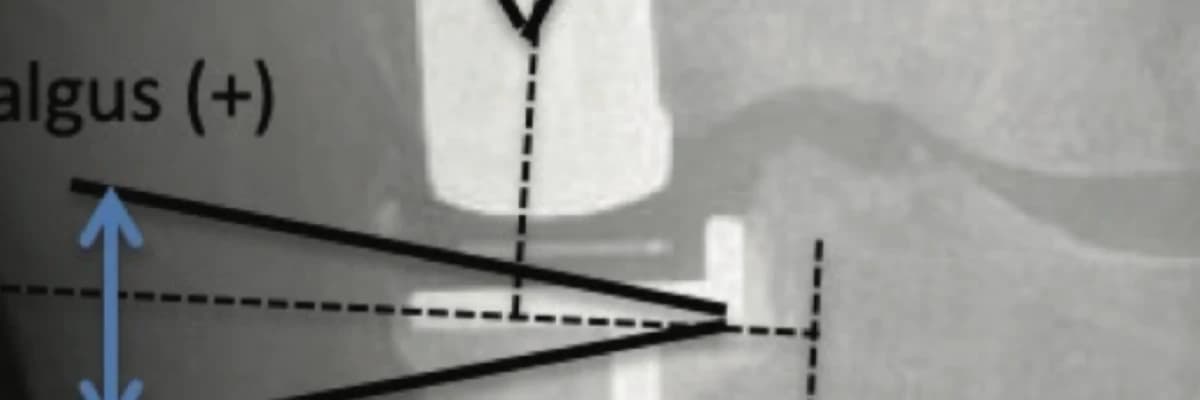

Methods: A retrospective study was established with patients who received 37 cementless and 41 hybrid UKA in a minimum 2-year follow-up period. The patients’ clinical outcomes were evaluated using the Oxford knee score, EuroQol-5 dimensions, EuroQol-visual analog scale, knee injury and osteoarthritis outcome score, and knee range of motion. The fixation of UKA components was evaluated with the varus-valgus angle of the tibial-femoral component, and the incidence of the radiolucent (RL) line at both the tibial and femoral component- bone interface on the radiograph.

Results: There was no significant difference in any clinical outcome measurement (p>0.05). There was no significant difference between the varus-valgus and flexion-extension angles of the femoral and tibial components in both groups (p>0.05). There were significantly more tibial RL in the hybrid

group than in the cementless group (p=0.025). There was no significant difference in the incidence of RL at the femoral component-bone interface (p=0.691).